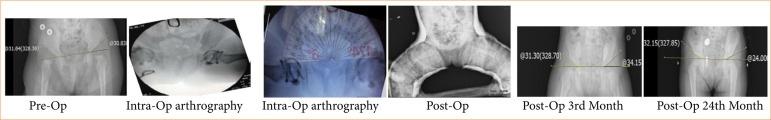

Purpose: To investigate the relationship between the cartilage acetabular index and acetabular development and secondary dysplasia.

Methods: A total of 58 hips underwent intraoperative arthrography-guided open reduction or limited open reduction due to developmental hip dysplasia between 2011 and 2015 was included in the study. We evaluated patients with acetabular angle 8º as group 2. Intraoperative acetabular cartilage index measurements were performed, and patients with low and high cartilage acetabular index were divided into two groups.

Results: There was a correlation between the cartilage acetabular index value, which indicates preoperative cartilage acetabular coverage, and acetabular development and secondary acetabular development.

Conclusion: The cartilage acetabular index is a technically easy and uncomplicated evaluation method that can be used to estimate acetabular development and should be used routinely together with the bone acetabular index.